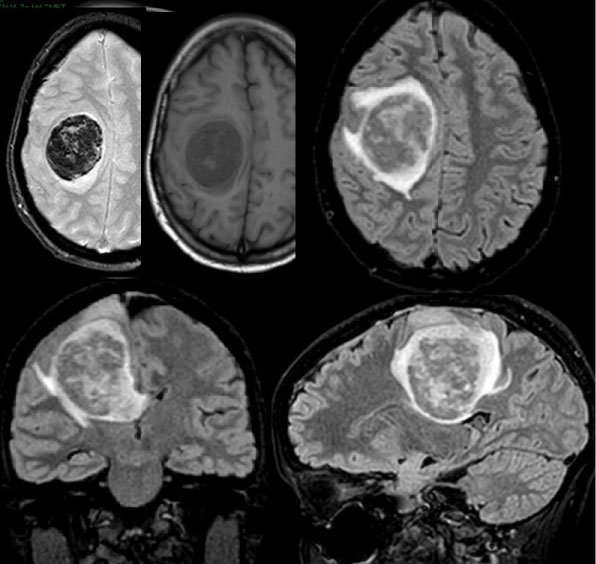

A 33-year-old woman in the 34th week of pregnancy presented with a mild left leg weakness. She was admitted to the Neurological division of our hospital. MRI scan of the brain showed a right rolandic lesion that extended to the middle third of corpus callosum and thalamic region, with a contrast-enhancing nodule, without spectroscopic evidence of necrosis (Figure 1). Two days after, the patient suddenly presented with a complete left hemiplegia. A second urgent MRI showed a dramatic increase in tumor volume due to intralesional hemorrhage (Figure 2). INR, PTT and platelet count were in normal ranges and the patient did not use antiplatelet drugs.

Figure 1: MRI performed at the onset of hemiparesis. View Figure 1